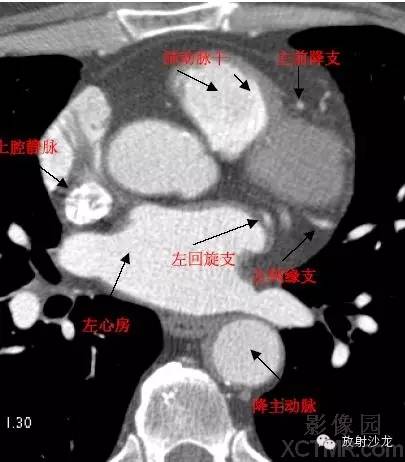

D. Aorta-Descending Aorta降主动脉

SVC –Superior Vena Cava上腔静脉

LMA -Left Main Artery冠状动脉左主干

LAD -Left Anterior Descending Artery左前降支

LCX -Left Circumflex Artery左回旋支

LMB -Left Obtuse Marginal Branch 左边缘支(钝缘支)